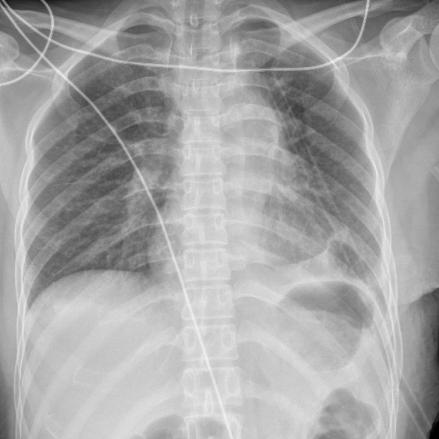

术后复查胸片显示: 肿瘤已被切除,肺复张好,无气胸无积液。